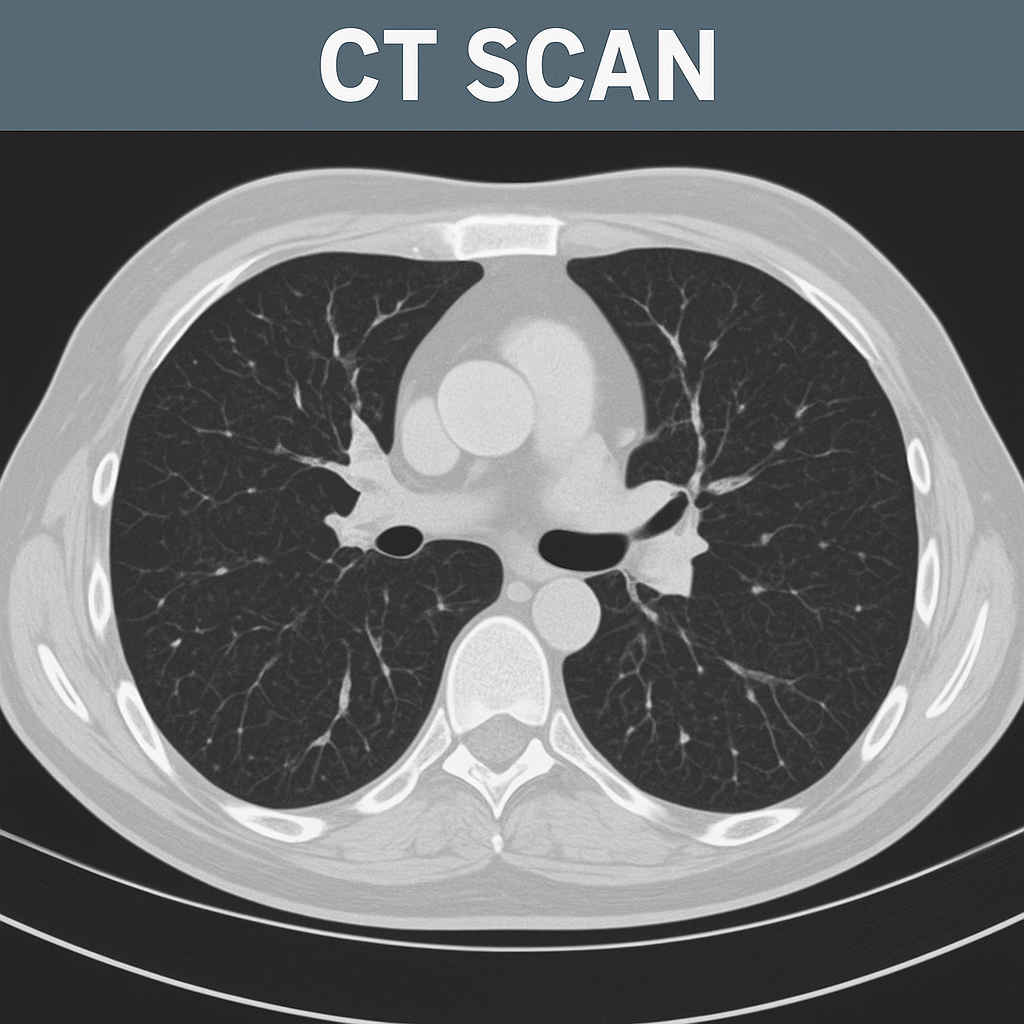

CT-scan (સીટી સ્કેન):

- સીટી સ્કેન એ એકસ રે કરતા વધારે ડિટેઈલમાં માહિતી આપતું અને થ્રીડી ઇમેજ પૂરું પાડતું ઈમેજિંગ સ્ટડી છે.

- સીટી સ્કેનમાં બોડીના જુદા જુદા એન્ગલ થી એક્સ રે લેવામાં આવે છે અને કમ્પ્યુટરની મદદથી બોડીના ક્રોસસેક્શન પિક્ચરને ક્રિએટ કરવામાં આવે છે.

- સીટી સ્કેનની મદદથી ઓર્ગન અને સોફ્ટ ટીસ્યુની કન્ડિશન જાણી શકાય છે.

- સીટી સ્કેનથી લંગ કૅન્સર, પલ્મોનરી એમ્બોલિઝમ અને ઇન્ફેક્શન આઈડેન્ટીફાઇ કરી શકાય છે.